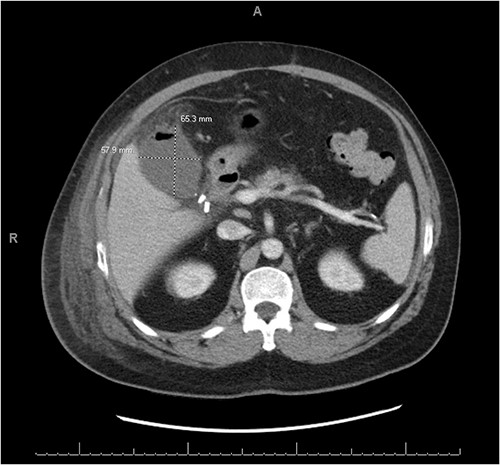

A 56-year-old male presented with a four-day history of right upper quadrant abdominal pain. One week prior to presentation, he underwent elective laparoscopic cholecystectomy at an outside hospital where his immediate postoperative course was complicated by a penicillin allergy reaction requiring ICU level care. Upon presentation to the emergency department labs were significant for mild leukocytosis of 11.1 K/uL with neutrophilia. Lipase and liver function tests were within normal limits. CT abdomen and pelvis showed a complex fluid density and foci of gas occupying the gallbladder fossa with concern for biloma or abscess (Fig. 1).

CT abdomen and pelvis with IV contrast demonstrating a complex fluid density with gaseous foci occupying the gallbladder fossa and measuring 6.5 cm × 5.8 cm × 5.5 cm.